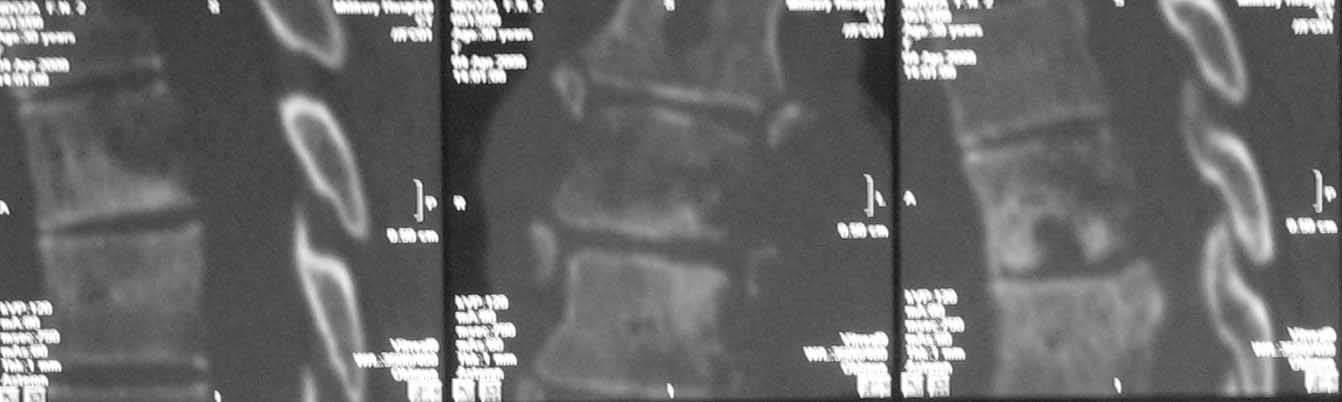

Случай действительно не стандартный и по результататам операционной ревизии обойтись без первичной иснрументации не удалось. первым этапом выполнена задняя ТПФ, вторым - левосторонняя торакотомия (соответственно максимальным изменениям паравертебральных тканей). при ревизии выявлено, что "жидкого" гноя нет, позвонки окружены гнойными вялыми, практически не кровоточащими грануляциями, тела позвонков Т5-9, включая 8 представляют собой "медовые соты ", фрагменты тел позвонков легко удаляются даже пинцетом. спинной мозг также сдавлен гнойными грануляциями. Тела Т5-9 удалены полностью. Установлен пористый никелид титана, обильно "сдобренный" цефобидом. Проточно-промывное дренирование.

spondylodiscit 6.jpg